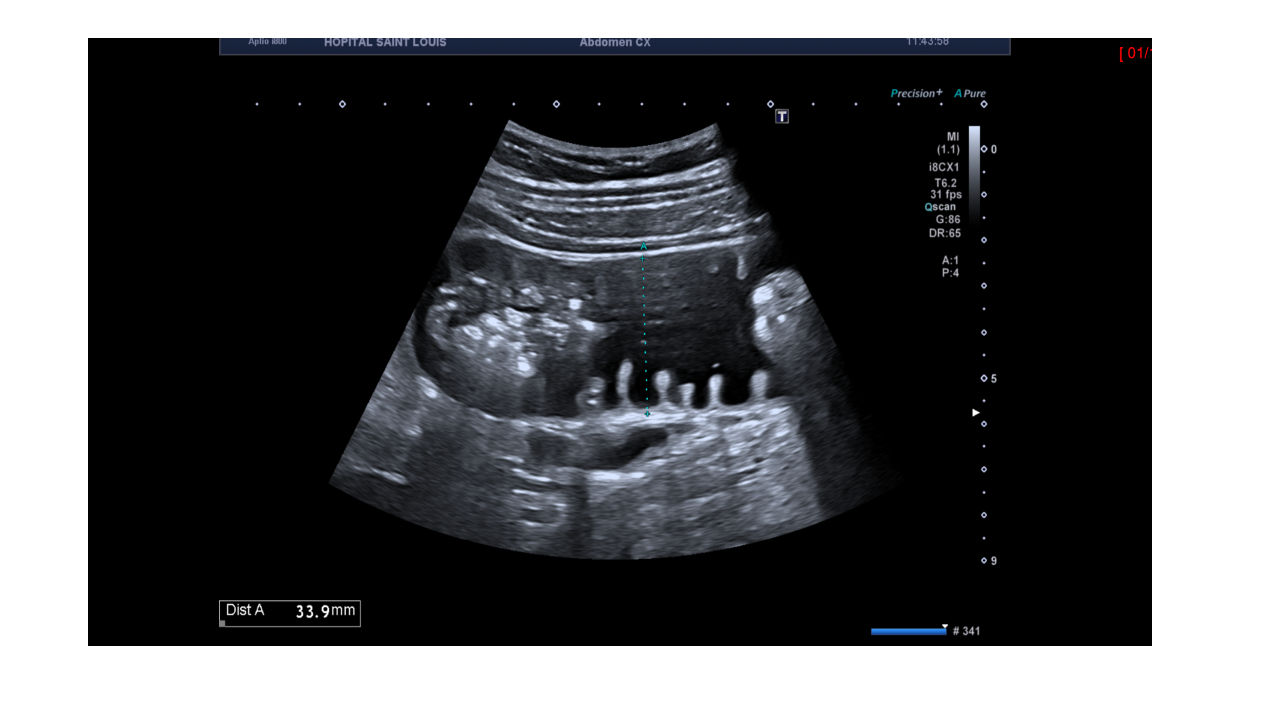

Le patient présente des douleurs abdominales, un balayage complémentaire est alors réalisé avec une fréquence d’émission augmentée pour mettre en évidence cette structure.

Une distension d'une anse grêle mesurée à 37mm de diamètre antéro postérieur est détectée.

Le diamètre d’une anse grêle ne doit pas dépasser 25mm .

Un apéristaltisme est ausi observé.

Le patient est alors adressé au scanner pour compléter l’examen.

Après la réalisation du scanner, le patient se retrouve hospitalisé pour un syndrome occlusif .